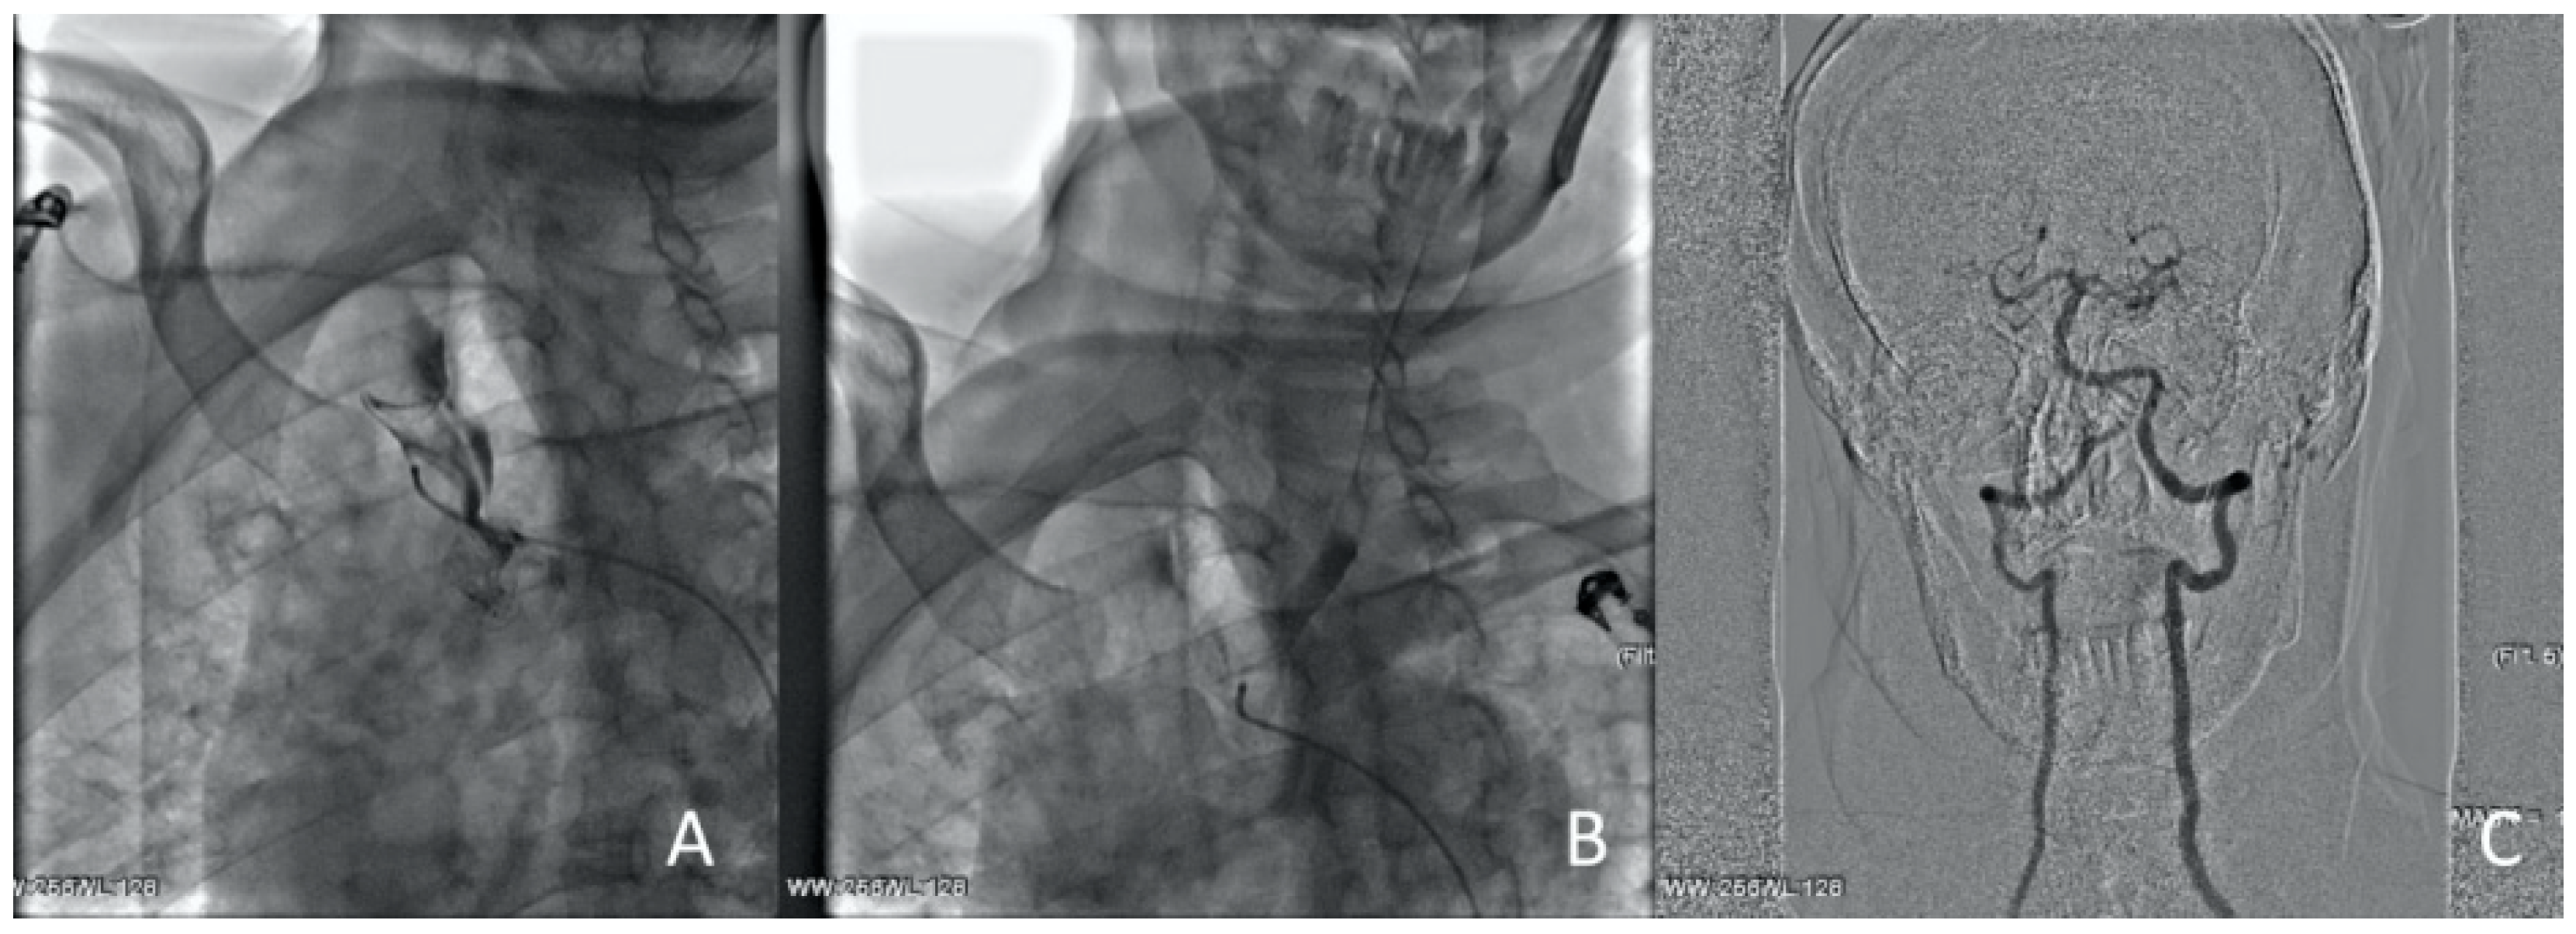

The left hemisphere circulation was restored in 90 min from the onset of the symptoms. The antegrade cannulation of the right CCA was technically impossible due to true lumen compression. Within 5 min, a retrograde puncture of the right CCA under ultrasound control was performed (Figure 12).

Figure 12.

Clinical Case 2, Patient S., male, 60 years old. Retrograde puncture of the right ICA.

The guide catheter was introduced into the descending aorta, and then into the left iliac artery, where it was externalized. It was decided not to remove the retrograde guide catheter from the CCA before installing the stent, since the compression during hemostasis could complicate the procedure. On the second guide catheter from the ICA orifice with protrusion into the aorta, a self-opening stent of 6.0 × 120 mm was implanted.

However, control angiography showed the absence of blood flow through the ICA due to the spread of hematoma to the C1 segment of the ICA. A cone stent of 8.0/10.0 × 40 mm was positioned in the ICA, with previously implanted stent overlap. The blood flow was totally restored. Right hemisphere revascularization was performed at 140 min from the onset of symptoms. Control angiography showed a complete restoration of cerebral circulation to the level of TICI-III (Figure 13).

Figure 13.

Clinical Case 2, Patient S., male, 60 years old. Right CCA revascularization. (A) Implantation of a 6.0 × 120 mm stent in CCA. No blood flow in ICA due to hematoma transition to the C1 segment. (B) Cone stent 8.0/10.0 × 40 mm implantation. Right hemisphere blood flow to TICI 3 level was totally restored.